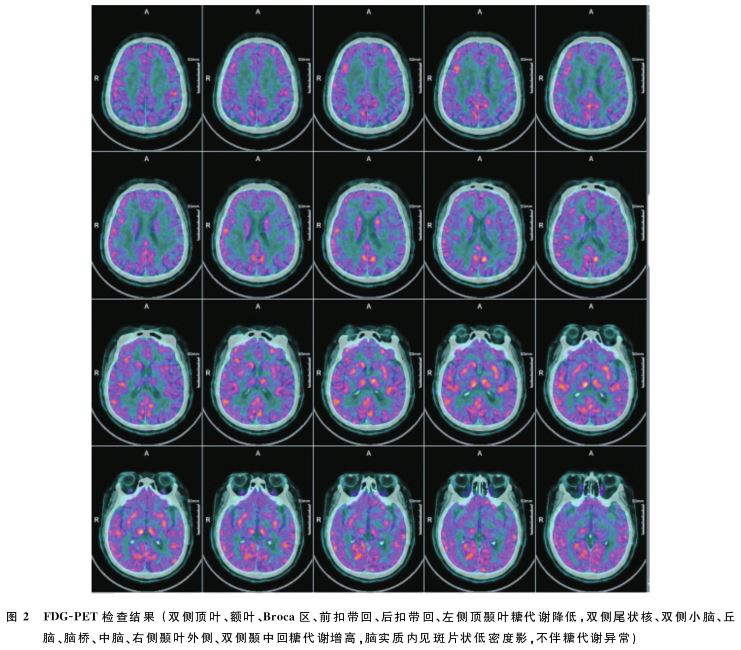

患者,女性,54岁,因“行走不稳、言语笨拙1周”于2022年6月来本院就诊。1周前无明显诱因出现行走不稳、言语笨拙,一过性眩晕,可在他人搀扶下行走,言语笨拙类似吟诗样。既往否认饮酒史、特殊药物及毒物服用史;家族中无类似疾病病史。神经系统查体:意识水平及意识内容正常,无失语,小脑性语言,概测视野正常,双侧水平眼震,四肢肌力正常、肌张力略降低,共济失调步态,双侧指鼻试验不稳准,双侧快速轮替试验笨拙,双侧跟膝胫试验欠稳准,昂白氏征睁眼及闭眼均不稳准,左侧病理征阳性可疑,余体格检查未见明显异常。改良Rankin量表(m RS)4分,国际合作共济失调量表(ICARS)37分,共济失调等级量表(SARA)13分。以“小脑共济失调”收入院。实验室检查结果:游离三碘甲状腺原氨酸(FT3)2.37pmol/L(参考值3.1~6.8pmol/L)、总三碘甲状腺原氨酸(T3)0.74nmol/L(参考值1.35~3.15nmol/L)、总甲状腺素(T4)54.2nmol/L(参考值70~156nmol/L)、促甲状腺激素(TSH)0.456 m IU/L(参考值0.372~4.94m IU/L)、抗甲状腺球蛋白抗体(Tg Ab)53.7%(参考值0~35%)、抗甲状腺微粒体抗体(ATM)51.6%(参考值0~35%)、抗甲状腺过氧化物酶抗体(TPOAb)155.2IU/ml(参考值0~34IU/ml)、甲状旁腺激素(PTH)82.23pg/ml(参考值15~65pg/ml)。人附睾蛋白4(HE4)91.89pmol/L(参考值<140 pmol/L)、糖类抗原242(CA242)20.94U/ml(参考值<20 U/ml)。糖化血红蛋白4.7%(参考值4.6~6.0%)。甲状腺超声:甲状腺双叶结节(ACR-TIRADS:1、2及3类)。头颅MRI平扫(图1):双侧小脑半球、右侧基底节区、半卵圆中心、放射冠区及左侧额叶腔隙性脑梗死及软化灶;DWI像未见异常。脑电图正常。肌电图:双下肢深感觉径路传到皮层段波幅下降。胸部CT未见明显异常。脑脊液常规生化检查:葡萄糖4.5 mmol/L(参考值2.2~3.9mmol/L),其余正常。脑脊液及血清行自身免疫性脑炎、中枢神经系统脱髓鞘病及副瘤综合征抗体检测:抗GAD65抗体Ig G阳性(1∶100,CBA法)。FDG-PET(图2):双侧顶叶、额叶、Broca区、前扣带回、后扣带回、左侧顶颞叶糖代谢降低,双侧尾状核、双侧小脑、丘脑、脑桥、中脑、右侧颞叶外侧、双侧颞中回糖代谢增高,脑实质内见斑片状低密度影,不伴糖代谢异常。全身FDG-PET未见恶性肿瘤表现。诊治过程:结合患者临床资料及相关辅助检查,诊断为伴甲状腺炎的抗GAD65抗体阳性自身免疫性脑炎,给予人类免疫球蛋白及大剂量激素冲击治疗,激素减量,后长期口服小剂量激素维持治疗,共济失调症状明显好转,m RS评分1分,ICARS评分22分,SARA评分9分。2022年8月首次复诊:患者病情平稳,为强化免疫治疗,给予环磷酰胺每月1次静点。复查头颅MRI较前未见明显变化,甲状腺功能各项指标均恢复正常,血清抗GAD65抗体滴度为1∶10,后患者由于疫情无法复诊,导致共济失调症状加重,需他人搀扶才可行走数米。于2023年4月来院行环磷酰胺治疗后,症状再次好转,可独立行走数百米。2023年8月复查,环磷酰胺累积剂量达8g,患者症状稳定。

抗GAD65抗体阳性AE不同的起病形式,其头部MRI及FDG-PET的影像学表现不尽相同。头颅MRI有助于区分起病形式,如急性起病患者的头颅MRI上极少出现小脑萎缩,慢性起病患者头颅MRI可表现为不对称小脑萎缩,尤其小脑蚓部萎缩[14]。FDG-PET葡萄糖代谢异常早于组织结构改变,在临床症状出现前或头颅MRI阴性者,可以通过FDG-PET检测到异常的葡萄糖代谢,提高诊断该病的敏感性。目前认为糖代谢变化与AE的抗体类型及疾病活动性显著相关,且代谢梯度的变化程度与病情严重程度呈正相关。如GABABR脑炎颞叶内侧、海马高代谢[15]。NMDAR脑炎急性期从额颞部至枕部代谢梯度递减[16];LGI1脑炎在全脑普遍低代谢背景下壳核、基底节区及海马高代谢。有关抗GAD65抗体脑炎FDG-PET葡萄糖代谢文献报道较少。部分抗GAD65抗体阳性AE患者单侧小脑半球灌注及葡萄糖代谢减少,在顶叶、额叶、枕叶、颞叶和海马等皮质区域出现低代谢[14]。而本例患者双侧顶叶、额叶、Broca区、前扣带回、后扣带回、左侧顶颞叶糖代谢降低,双侧尾状核、双侧小脑、丘脑、脑桥、中脑、右侧颞叶外侧、双侧颞中回糖代谢增高,推测这与该病导致广泛性脑网络连接损害,机体的补偿机制使脑默认网络连接增加有关[14]。在疾病不同阶段,糖代谢表现出由增高到降低的动态规律。在急性期呈高代谢,恢复期及复发时呈低代谢。症状好转后,糖代谢可恢复正常。本例患者头部MRI显示小脑无萎缩,未见异常信号表现,而FDG-PET提示皮层广泛糖代谢减低背景下,双侧尾状核、双侧小脑、丘脑、脑桥、中脑糖代谢增高,结合患者发病特点,考虑与患者急性起病,病程较短,尚处在炎症活动急性期有关,需要在将来的随访中观察影像学动态变化。有文献报道抗GAD65抗体阳性AE还可快速进展为额颞叶痴呆[17],本例患者FDG-PET上已经显示与认知相关脑区代谢异常,应警惕未来发生认知障碍。